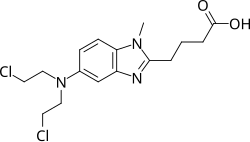

Bendamustine

| Formula | C16H21Cl2N3O2 |

Bendamustine, sold under the brand name Treanda among others, is a chemotherapy medication used in the treatment of chronic lymphocytic leukemia (CLL), multiple myeloma, and non-Hodgkin's lymphoma.[4][5] It is given by injection into a vein.[4]

Common side effects include low blood cell counts, fever, nausea, diarrhea, loss of appetite, cough, and rash.[4] Other severe side effects include allergic reactions and increased risk of infection.[4] Use in pregnancy is known to harm the baby.[4] Bendamustine is in the alkylating agents drug class.[4] It works by interfering with the function of DNA and RNA.[4]

Bendamustine was approved for medical use in the United States in 2008.[4] It is on the World Health Organization's List of Essential Medicines.[6][7] It was originally made from nitrogen mustard.[4]

Bendamustine is a white, water-soluble microcrystalline powder with amphoteric properties. It acts as an alkylating agent causing intra-strand and inter-strand cross-links between DNA bases.